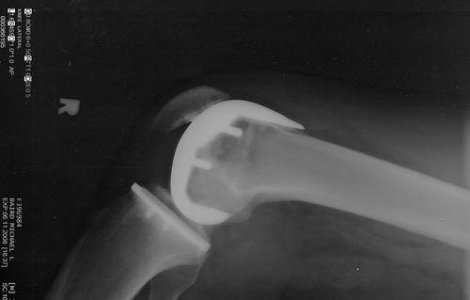

Pacientii romani diagnosticati cu artroza pot beneficia, si la Hyperclinica MedLife Grivita din Bucuresti, de o terapie inovatoare contra acestei afectiuni, datorita careia se pot bucura de doi ani de confort si de sansa de a amana protezarea, potrivit specialistilor in ortopedie.

Artroza, afectiune care afecteaza 200.000 de romani cu varste cuprinse intre 25 si 45 de ani, poate fi vindecata cu tratamente inovatoare ce folosesc ser din sangele pacientului, potrivit specialistilor